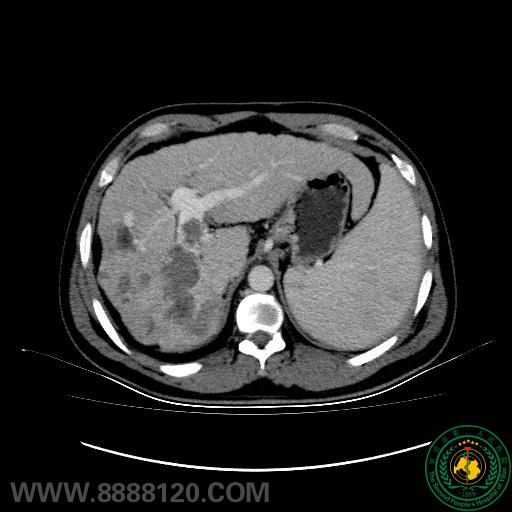

以前,肝癌合并门静脉癌栓为肝癌经肝动脉化疗栓塞术(TACE)的相对禁忌症,患者生存期短,即便采用姑息性化疗栓塞术,术后也可能因肝功能衰竭、门静脉高压加重而导致上消化道出血,且癌栓进行性扩散会形成恶性循环,使得患者肝功能显著下降。近期,我院影像科介入室对此类患者的治疗取得了突破。具体方案为:先行门静脉支架植入开通门静脉通路,再行肝动脉化疗栓塞术。

我们通过对几例行肝动脉化疗栓塞联合门静脉支架置入术患者随访,发现肿瘤原发病灶及癌栓控制均良好,提示该法具有以下优点:1、恢复门静脉血流动力学,减少门脉高压性消化道出血机率;2、促进正常肝叶过度灌注、代偿性肥大,纠正或改善肝功,为二期外科手术提供条件;3、控制癌栓门静脉的进一步侵袭、蔓延,利于TACE治疗效果。